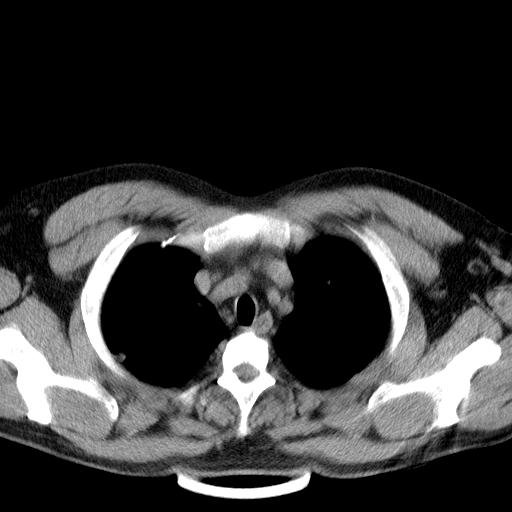

患者男性 35 主因发热咳嗽四天,血象不高,心肺听诊未见异常,无其它病史及传染病接触史。

两肺散在大小不等小结节影,下野较多,纵隔淋巴结增大。考虑:1、慢性血播性肺结核;2、霉菌病?3转移瘤待排。

两肺多发结节,部分病灶边缘不清,且示毛玻璃影。分布特点为沿血管支气管分布。

结合临床考虑;1,炎性肉芽肿性病变;霉菌?过敏性肺炎?2,韦格氏肉芽肿。3,转移瘤。

双肺及胸膜下见多发结节影,最大直径约0.4,内密度均匀,中纵隔腔静脉后见小淋巴结影。